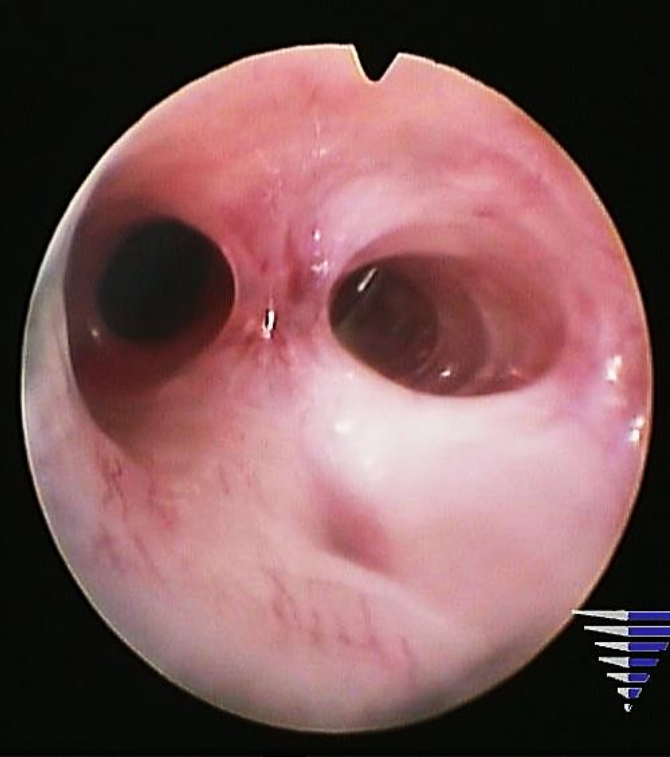

Paciente de 35 anos, G1A1, refere ausência de menstruação desde que sofreu um aborto espontâneo precoce tratado com curetagem uterina há 6 meses. Antes dessa gestação, tinha ciclos regulares e mensais. Sem outras queixas. Foi submetida a uma vídeo-histeroscopia, cuja imagem está apresentada pela Figura 1 abaixo:

Figura 1

Qual a hipótese diagnóstica?